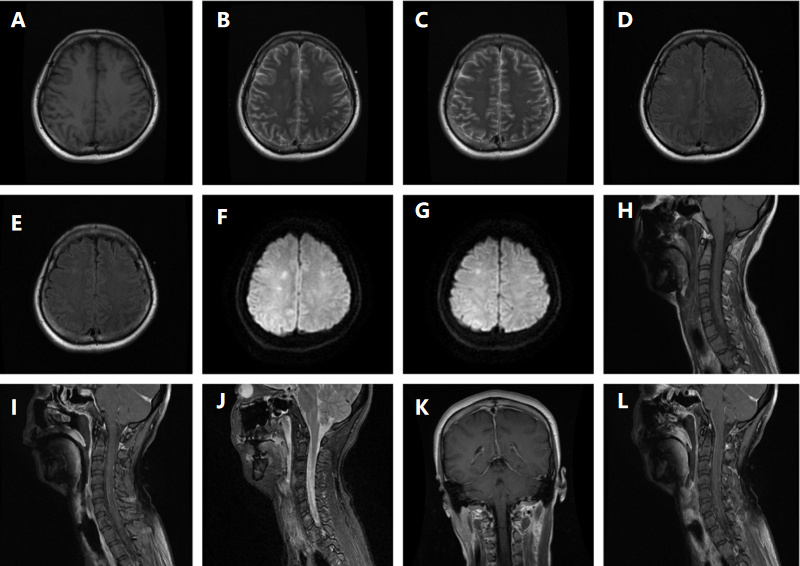

1 资料与方法 1.1 入院病历资料患者女性,36岁,因“反复发热7 d”于2025年6月25日入住本院感染科。入院7 d前出现发热,最高体温39℃,伴畏冷、寒战,6月24日就诊当地医院,查血常规未见明显异常,C反应蛋白26.2 mg/L,红细胞沉降率50 mm/h,纤维蛋白原5.69 g/L,血清生化,丙氨酸氨基转移酶331.9 U/L,天冬氨酸氨基转移酶246.6 U/L,谷氨酰转移酶120.7 U/L, 碱性磷酸酶109.1 U/L,胸部CT:左下肺异常密度影,炎症性病变可能”, 予保肝、“左氧氟沙星0.5 g静滴, 1次/d、头孢曲松2 g静滴, 1次/d”抗感染治疗,但仍反复发热,转诊本院,复查胸部CT:左肺下叶炎症改变,考虑感染性病变(图 1)。既往体健,否认任何毒物、药物上瘾史。入院查体:体温37℃,脉搏77次/min,呼吸20次/min,血压97/55 mmHg。神志清楚,精神疲乏,双肺呼吸音稍粗,双肺未闻及干湿性啰音。神经系统查体未见异常。入院诊断:社区获得性肺炎; 肝功能不全。

| 图 1 胸部CT提示: 左肺下叶见斑片状高密度影,部分呈磨玻璃样改变,可见支气管充气征,边缘模糊,密度不均(箭头所示) |